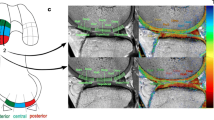

Measurement of graft signal intensity

MRI data were transferred to a workstation for offline quantification of T1rho and T2 map values. Three intra-articular locations of the graft at which slice planes could be made perpendicular to the long axis of the graft were defined on sagittal images. Those included the midpoint between femoral and tibial tunnel outlets and points 1 cm proximal and 1 cm distal to the midpoint. Segmentation was performed manually on the three slice planes to segregate the purely tendinous portion from surrounding synovial tissue. Regions of interests (ROIs) set on the purely tendinous portion of the graft were measured for relaxation times of T1rho and T2 map sequences, and the mean value of the three slice planes was calculated. Mean values for AMB and PLB were measured separately.

On MRI examination, the T1rho sequence was able to visualize tendinous portions of the AMB and PLB more clearly than the T2 map sequence in gray-scale images, and easily segregated the purely tendinous portion from surrounding synovial tissue (Fig. 1). Color-coded images were capable of visualizing the tendinous portion of the graft in both sequences. Mean T1rho values gradually decreased during the first year after ACL reconstruction (Fig. 2). Such trends were more prominent in AMB than in PLB. In contrast, reduction of T2 map values was dull in both AMB and PLB during the first year. When temporal changes were individually focused, T1rho values decreased more consistently among patients than T2 map values (Fig. 3).